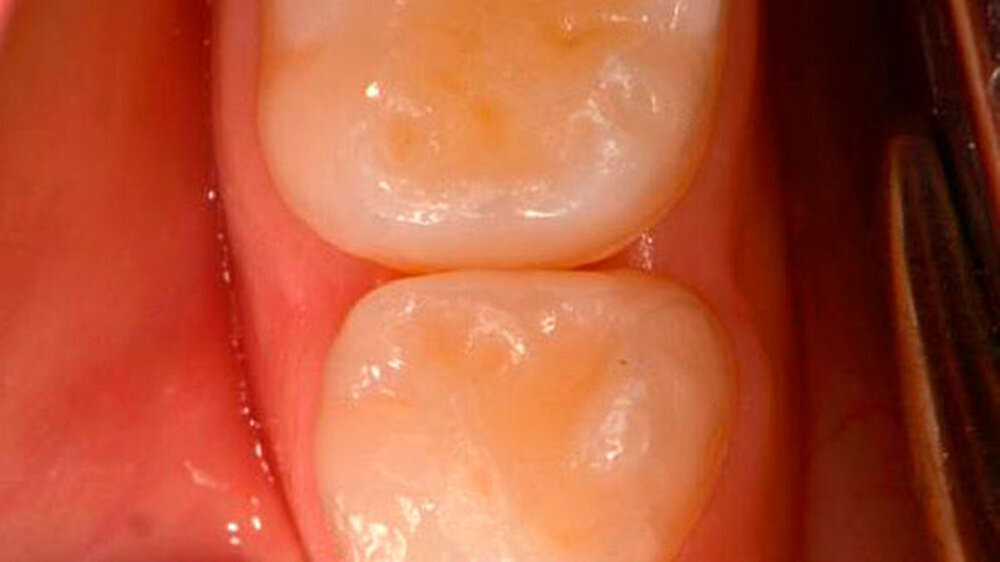

Zuerst ist fast immer der Vierer distal betroffen, dann folgt der Fünfer mesial. Milchzähne haben durchschnittlich nur eine Schmelzdicke von einem Millimeter, der Schmelz am Vierer distal ist noch dünner, das heißt noch anfälliger. Der Kontaktpunkt 4/5 bildet sich erst in der Gebrauchsphase des Milchgebisses, wobei er zusätzlich häufig flächiger wird. Die anderen Kontaktpunkte im Milchgebiss lösen sich durch die physiologische Lückenbildung eher auf, das Kontaktpunktkariesrisiko sinkt also.

So wie wir die Eltern zur Zahnpflege mit der Zahnbürste anleiten, so leite ich sie zur Verwendung von Zahnseide an: Bei jedem Vorsorgetermin prüfe ich selbst mit der Zahnseide, ob ein Kontaktpunkt vorhanden ist und ob sich dort Plaque befindet. Ich zeige den Eltern die Plaque auf der Zahnseide. Wenn Plaque vorhanden ist, zeige ich den Eltern die Anwendung von Zahnseide mithilfe eines Zahnseidensticks oder des üblichen Fadens - flaches Band finde ich besser als eine runde Zahnseide.

Danach lasse ich die Eltern üben, damit sie in der Anwendung bei ihrem Kind sicher sind. Denn die Pflegehandlung der Eltern soll für das Kind angenehm sein. So müssen manche Eltern schon bei ihrem zweieinhalbjährigen Kind Zahnseide anwenden, manche nur oben oder nur unten und manche gar nicht. Durch dieses individuelle Vorgehen machen fast alle Eltern mit. Übrigens: Interdentalraumbürstchen sind theoretisch anwendbar, passen aber in der Realität nur im Ausnahmefall in die Zahnzwischenräume der Milchmolaren.